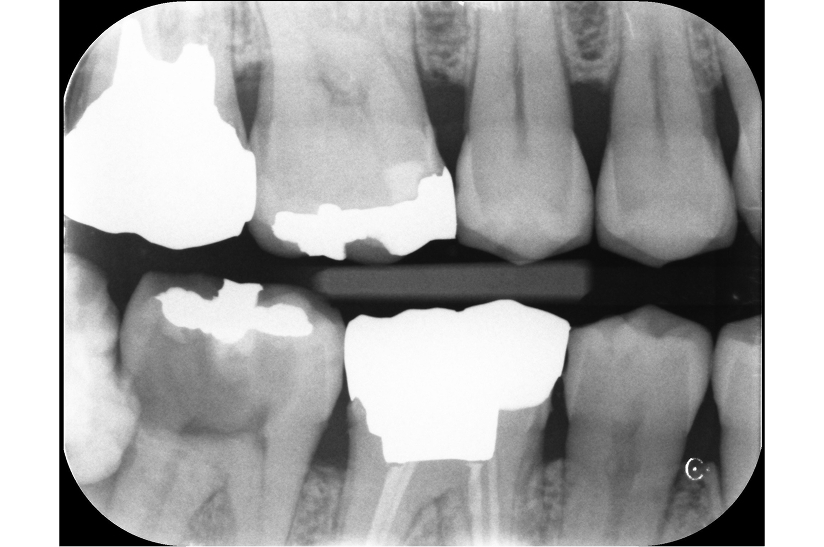

他院での治療を丁寧にリカバリーした症例

タップで写真の拡大ができます。

Before

After

Under Treatment

主訴

他院で治療をしてもらってからズキズキ痛み、噛むときも痛い。

治療内容

イニシャルトリートメント(根管治療・大臼歯)、ファイバーポストコア

治療期間

1回

治療費用

176,000

治療の

リスク

根尖部透過像が完全に消失しない可能性があります